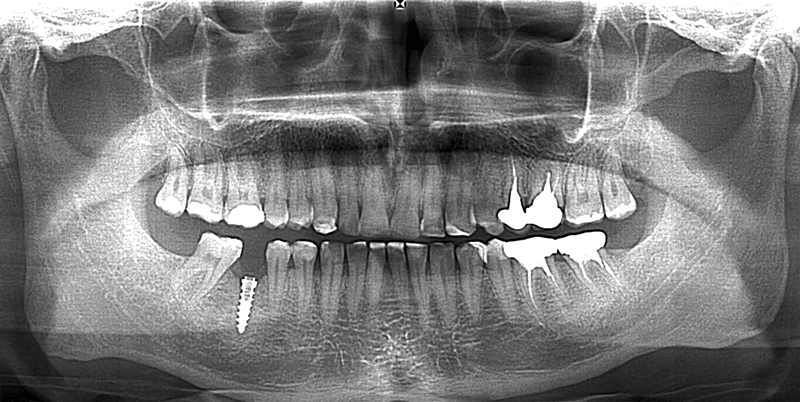

Chapter 20. Dental implantology